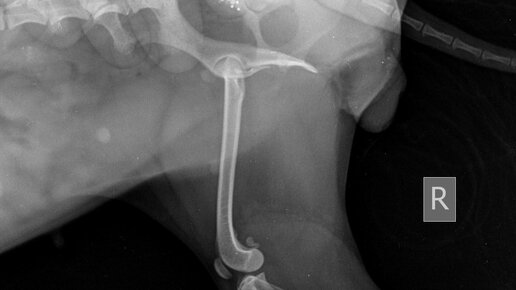

Диагностика и лечение разрыва ПКС, TPLO у собак

От разрывов ПКС - до ремонта чкс у собак

В спорте разрыв передней крестообразной связки (ПКС) - очень распространенная травма. Та же самая травма часто поражает собак (даже тех, которые не являются спортсменами), но у собак это называется разрывом чкс...